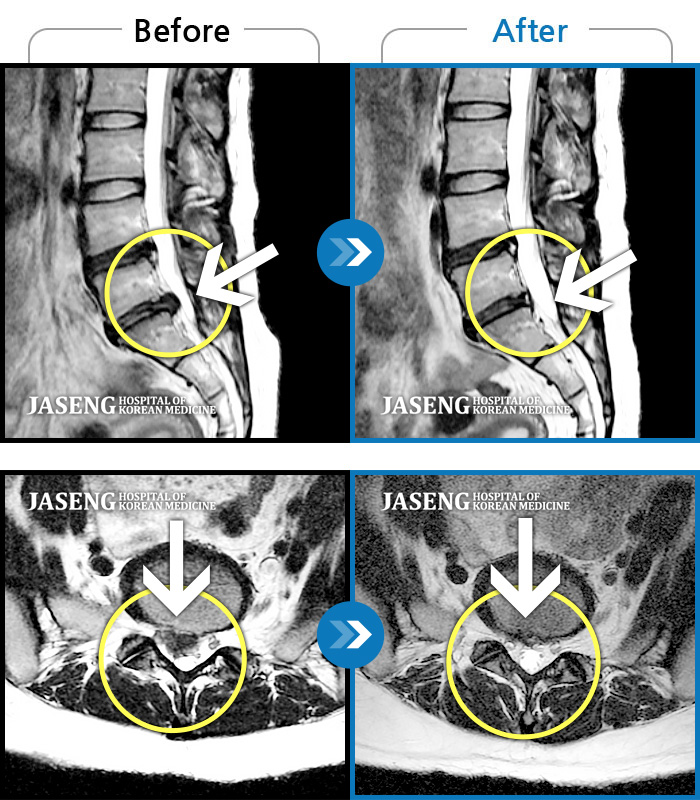

MRI 치료사례

허리통증, 우측 엉덩이 통증